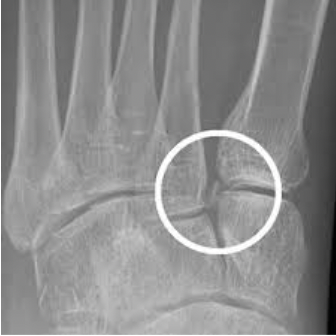

Lisfranc Fractures-Dislocations

Lisfranc injuries involve disruption of the tarsometatarsal articulation between the second metatarsal base and medial cuneiform, stabilized by the Lisfranc ligament. While severe injuries may be obvious on initial imaging, subtle cases may only demonstrate widening between the first and second metatarsals or a small avulsion “fleck sign.” Missed Lisfranc injuries predictably result in painful post‑traumatic midfoot arthritis. When radiographs are inconclusive, MRI is helpful to evaluate for ligamentous injury and occult fractures. Prompt non‑weightbearing immobilization and orthopedic referral are critical.